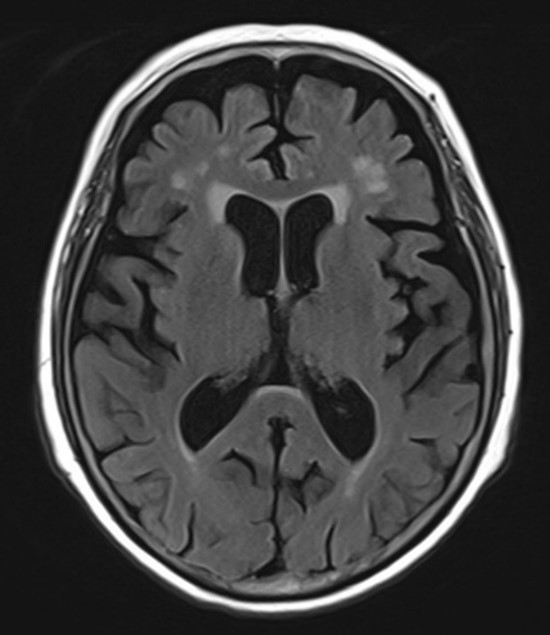

그림17.jpg 촬영 일시: 2025.05.22

치매 MRI 결과를 보니까

다행히 급성 뇌경색 같은 응급 상황은 아니었지만,

연령에 비해서 뇌 위축이 진행되어 있는 상태였어요.

그리고 인지기능 검사에서도

유의미한 저하가 확인되었습니다.

초기 치매 진단이었죠.